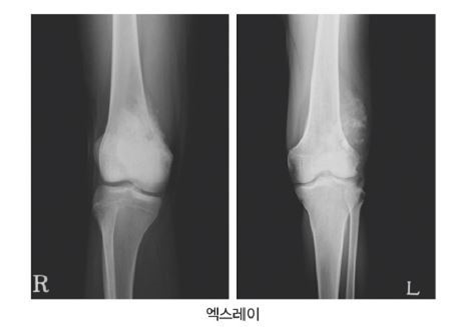

골종양은 크게 연골종양, 골종양, 전이성 종양 및 기타 골종양으로 나뉜다. 연골종양 중 연골종은 연골세포로 구성된 비교적 흔한 양성종양으로 내연골종과 외연골종으로 나눌 수 있다. 주로 젊은 사람들에게 발생하며 다발성이며 일반적으로 손가락과 발가락의 뼈에서 발견됩니다.

이 밖에도 골연골종(osteochondroma)과 골연골육종(osteochondrosarcoma)이 있는데, 골연골육종은 겨드랑이 연골 종양을 말하며 주로 견갑골, 갈비뼈, 엉덩이뼈에 발생하며 악성 골암의 20%를 차지하며 대부분 중년 이후에 발생한다. 골암은 골암에 비해 골종(osteoma)과 골육종(osteosarcoma)으로 나뉘는데 골종은 골조직의 종양으로 비교적 드문 단일 양성 종양으로 가드너 증후군이나 가족력에 의해 발생하며 전형적인 악성 골종양이다. 모든 뼈 종양의 약 10%에서 출혈과 괴사를 동반합니다. 어떤 경우에는 골 파괴 또는 불규칙한 골 형성 경향이 명백합니다. 전이성 종양은 뼈 이외의 상피 조직에서 발생합니다. 악성 종양이 전이되어 혈액과 골수에 종양을 형성한 경우입니다. 뼈로 전이되기 쉬운 종양에는 유방암, 전립선암, 갑상선암 및 폐암이 포함됩니다.